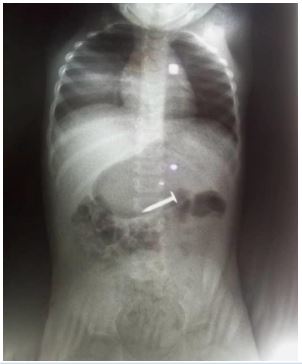

She presented with a plain abdominal radiograph which showed a FB (nail) in the body of the stomach (Figure 1) This was done about 6 hours prior to the presentation at our facility. A repeat radiograph done at the presentation showed the FB (nail) at the region of the terminal ileum (Figure 2). She was commenced on nil per oral, intravenous fluids and monitoring (clinical and radiological). She had two additional plain abdominal radiographs, (Figure 3, 24 hours on admission) and (Figure 4, on day 3). The vital signs remained stable and the abdominal examinations remained equivocal throughout the period of admission. She was discharged following a repeat radiograph which showed no evidence of FB in the GIT.

Figure 3: AP + Lateral view of plain abdominal radiograph. (24 hours admission).

Figure 4: AP view of plain abdominal radiograph (Day 3).